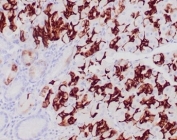

IHC: Formalin-fixed, paraffin-embedded human gastric carcinoma stained with MUC6 antibody (clone CLH5). HIER: steam section in pH6 citrate buffer for 20 min and allow to cool prior to testing.

IHC testing of FFPE human gastric carcinoma with MUC6 antibody (clone CLH5). HIER: steam section in pH6 citrate buffer for 20 min and allow to cool prior to testing. Image courtesy of Dr. Leonor David, IPATIMUP and Medical Faculty, University of Porto, Portugal.